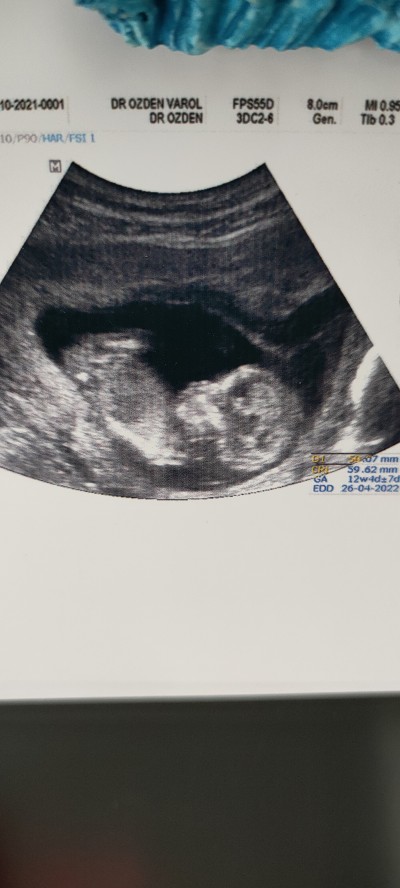

Merhaba cinsiyetini tahmin edebilecek biri var mı?

Gebelik haftası

Bebek kız konumunda

Bencede kiz canım banada öyle geldi

Kiz gibi duruyor Rabbım hayırlısını nasip etsin inş

Icime hemen kız dogdu maşallah sübhanallah allah bağışlasın:)

Kiz gibi canim rabbim sag salim kucagina almayi nasip etsin insallah